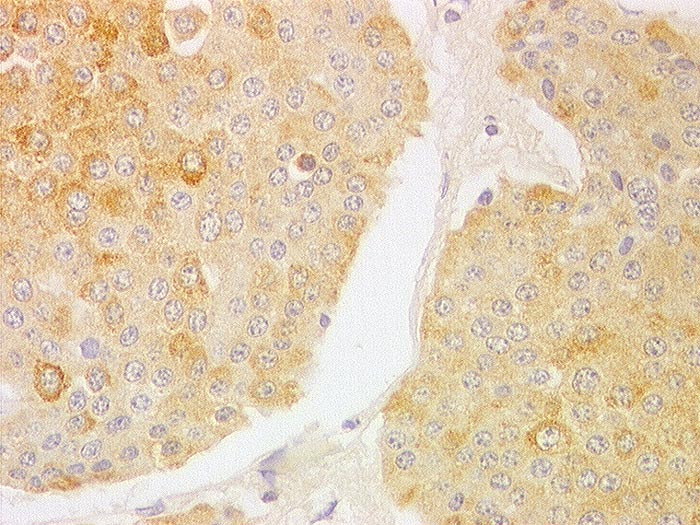

PathoPic ID 1244 - Neuroendokrines Karzinom des Ileums : Metastase

Neuroendokrines Karzinom des Ileums : Metastase

Leber

Monomorphe Tumorzellen in soliden Nestern. Runde Kerne mit Pfeffer und Salz Chromatin.

Immunhistochemie

Synaptophysin